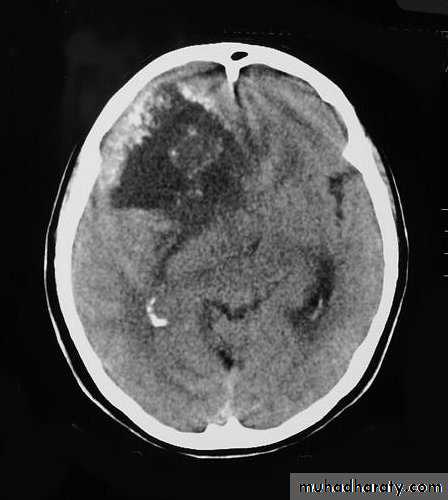

Malignant GliomaPre contrast CT

Malignant Glioma Post contrast CT